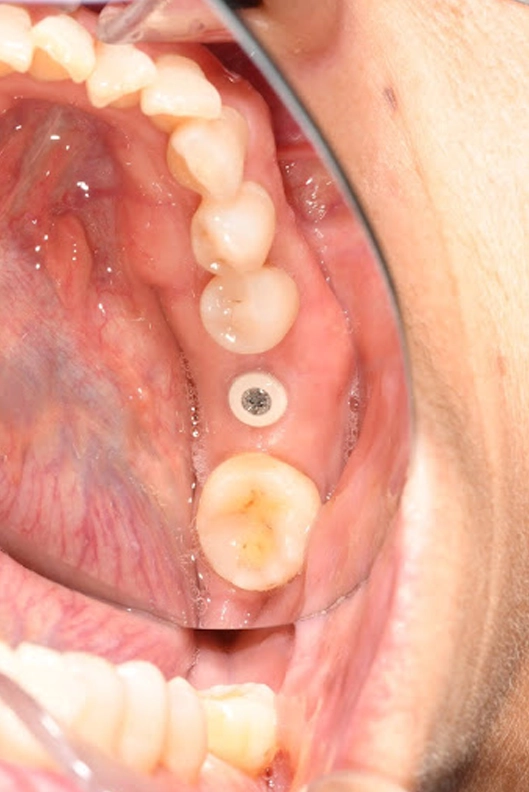

Lower (L) 1st molar:

Already restored with an implant and final crown, both functional and stable.

- Lower left first molar: The lower left first molar had already been restored with an implant and crown in an earlier stage of treatment. We included it in this case report as a reference point to show the stability and function of her implant work over time.